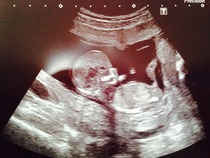

Here's some pickies for some ahh and oohhss was beautiful hearing the heart beats. Very overwelhming.

Congratulations Lady, lovely pictures.

Oh ladies those scan pictures are so lovely! Can't wait for mine now :)